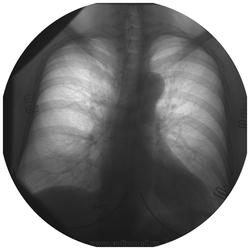

Уважаемые коллеги! Хотелось бы Вашего мнения. R-гр. ОГК в 2 проекциях - в правом корне доп. тень? Да, и прошу не удивляться "круглым" снимкам - вот так снимают у нас...

Бронхопульмональный лимфатический узел.

Мой вариант - сосуд в ортопроекции. И, опять-таки, на мой взгляд, на снимках в прямой и боковой проекциях указаны разные отделы.

Сосуд в ортопроекции.

Да, по прямой, ортоград...А вот то что на боковой, так то нуждается минимум в линеечке.

Согласен с сосудом. И на прямой он. И на боковой. Тоже он - сосуд. Но уже другой!) Посмотрите по взаиморасположению - относительно пространственных ориентиров - той же аорты (верхнего края дуги) - сосуд так интересно не меняет своё местонахождение, пусть и при различном объёме воздуха у пациента в груди.